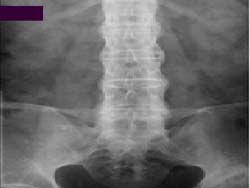

<°Á÷¼º

ôÃß¿°ÀÇ ¹æ»ç¼± »çÁø>